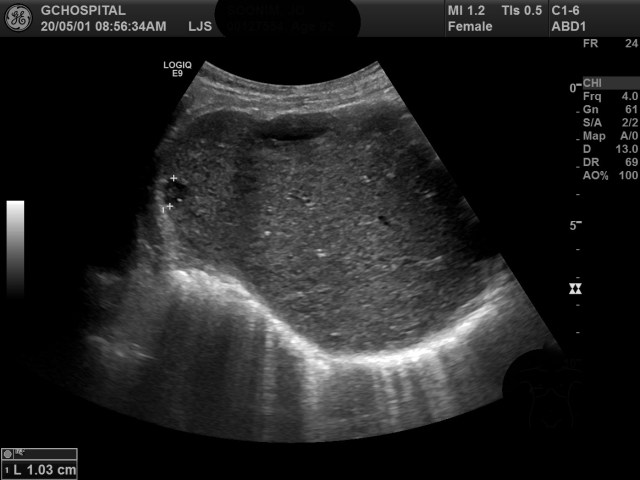

위는 검진초음파를 위해 내원한 분의 간초음파영상입니다. 탐촉자를 늑골 아래쪽에서 위로 올려서 간의 윗부분을 촬영한 영상입니다.

간 우엽의 앞쪽 피막 바로 밑부위에는 타원형의 단순낭종이 보이며, 커서로 표시한 곳에는 1센티미터 크기의 작은 원형병변이 보입니다. 경계가 분명하며 마찬가지로 간의 피막 바로 밑에 위치하기 때문에 단순낭종의 가능성을 가장 먼저 생각할 수 있지만, 병변 내부에는 비교적 밝고 뚜렷한 에코가 보이며, 단순낭종을 진단할 때 필요한 후방에코강조(posterior acoustic enhancement)소견이 보이지 않습니다.

촬영하던 당시 탐촉자를 어떻게 움직여서 촬영해도 늑골 아래쪽에서 보면 해당 병변 내부의 에코음영이 계속 확인되었으며, 후방에코강조소견도 확인할 수 없었기 때문에 단순낭종보다는 비전형적인 간혈관종의 가능성을 배제하기 어렵습니다.

앞서는 포커스가 해당 병변보다 더 아래쪽으로 비켜나있었기 때문에, 포커스를 병변부위로 맞추고, 최대한 내부의 에코가 보이지 않도록 조절해서 영상을 촬영해보았음에도, 병변 내부의 에코를 완전히 없애는건 불가능했습니다.